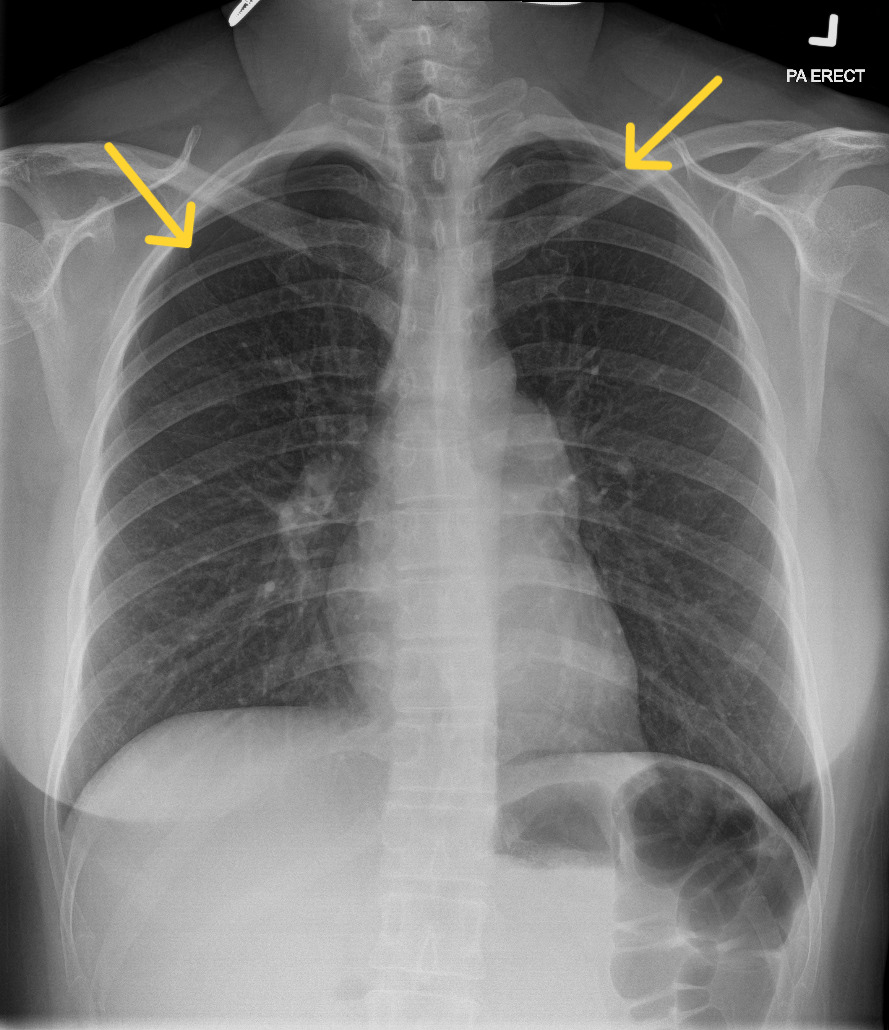

A 39-year-old Chinese woman presented to the Emergency Department with acute chest tightness and shortness of breath, which started after she completed an acupuncture session for her long-standing neck pain. Specifically, she underwent needle insertion at several acupoints, including GB21 (Jianjing), located at the crest of the trapezius muscle near the apices of the lungs. She had been well prior to acupuncture. On arrival, she was hemodynamically stable, afebrile, with normal oxygen saturations on room air. On examination, there was reduced air entry over the bilateral lung apices, but the rest of the systemic examination was unremarkable. A chest radiograph showed bilateral apical pneumothoraces, measuring up to 1.6cm on the right and 0.6cm on the left (apex-to-cupola distance) (Figure 1). Given her stable clinical status and absence of hemodynamic compromise, a trial of conservative management with supplemental oxygen therapy was given with close observation. Serial chest radiographs demonstrated resolution of the pneumothoraces, and she was discharged without the need for chest tube insertion.